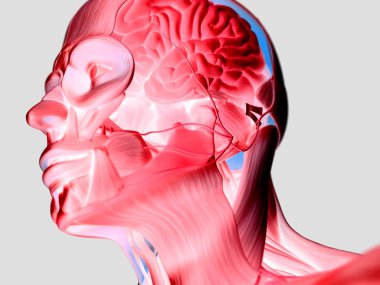

The arterial blood supply to the neck (carotids and vertebral arteries).